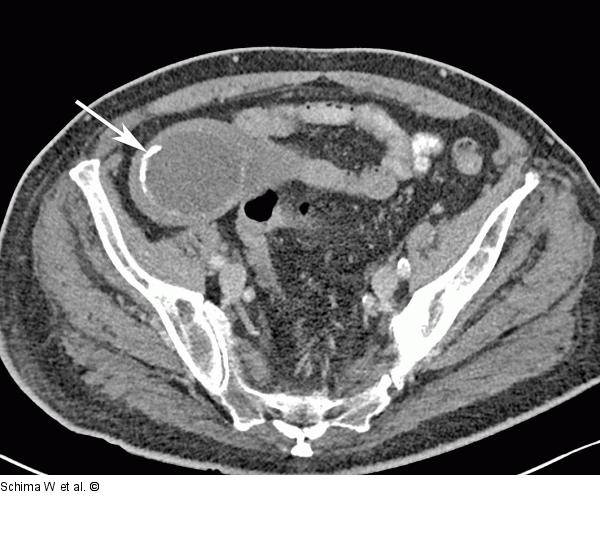

Abbildung 2a: MDCT Die MDCT (axiales Bild) zeigt die dickwandige zystische, zum Teil verkalkte Raumforderung im rechten Unterbauch (Pfeil). |

Die MDCT (axiales Bild) zeigt die dickwandige zystische, zum Teil verkalkte Raumforderung im rechten Unterbauch (Pfeil). |